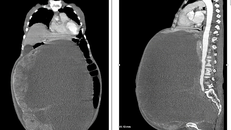

(Ngày Nay) - Khi phát hiện người bệnh bị viêm phúc mạc ruột thừa, các bác sĩ còn phát hiện người bệnh có phủ tạng đảo ngược hoàn toàn, trái tim và dạ dày nằm bên phải, còn gan và ruột thừa lại nằm bên trái.